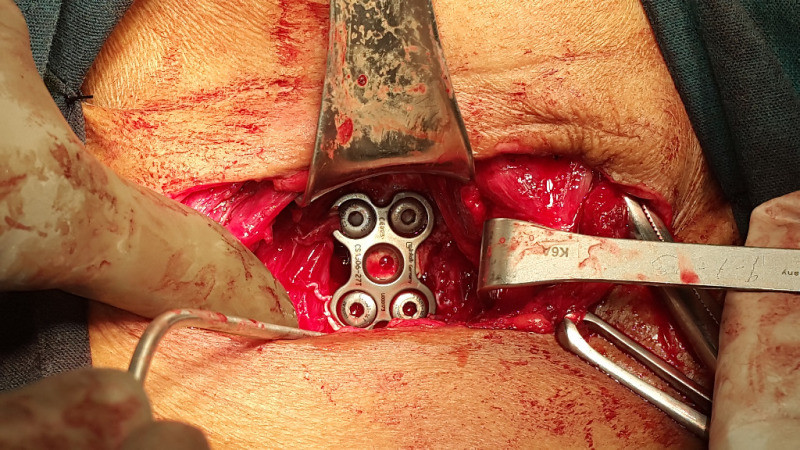

Cirugía endoscópica de columna e instrumentación

Envíado por Dr. Hugo Enrique Castro Cordero